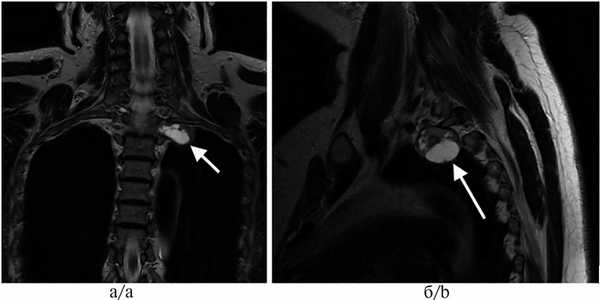

Рис. 2. Магнитно-резонансные томограммы пациента с апикальной нейрогенной опухолью, проникающей в межпозвонковое отверстие.

а — фронтальный срез, б — сагиттальный срез (опухоль указана стрелкой).

При опухолях по типу «песочных часов» (рис. 5) операцию выполняли мультидисциплинарной бригадой совместно с нейрохирургами. На первом этапе проводили ламинэктомию (гемиламинэктомию) с мобилизацией интраканального компонента опухоли, пересечением нервного корешка и погружением этого компонента в плевральную полость. Мобилизацию внутригрудного компонента и удаление опухоли осуществляли посредством ВАТС или при помощи одного из описанных выше доступов (надключичный, торакотомия, цервикостернотомия).

Рис. 5. Магнитно-резонансная томограмма пациента с опухолью по типу «песочных часов» (указана стрелками).